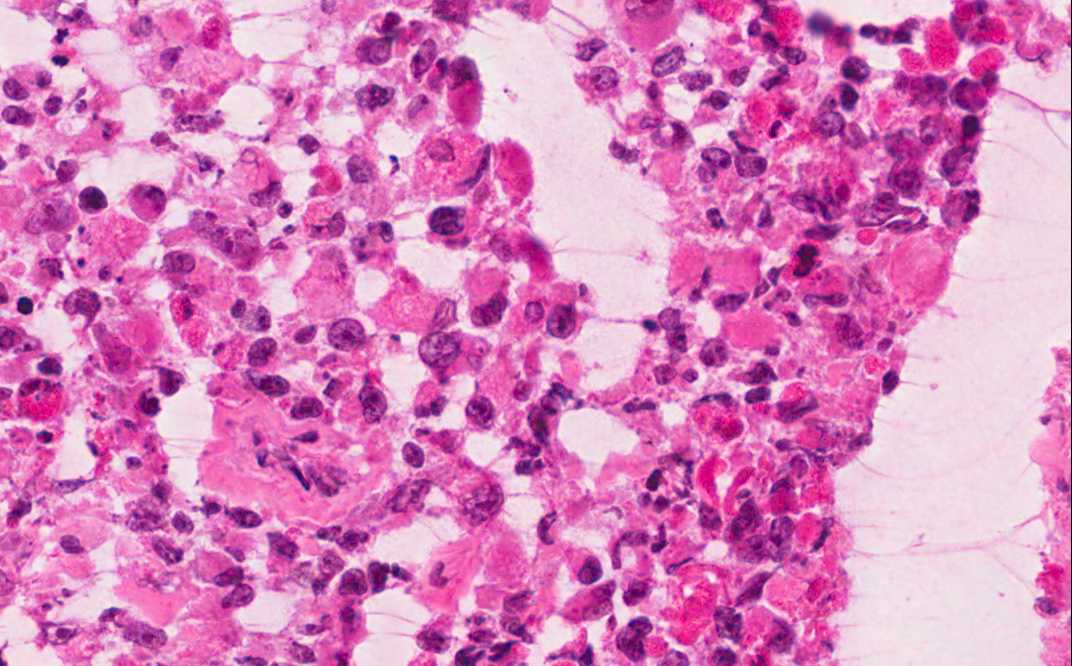

Hematoxylin & eosin

Area 1: The tumor is solidly packed with round to oval cells of comparable size but there is a definitive variation of cellular size. The nuclei are large and have prominent nucleoli. The larger cells have amphophilic cytoplasm and eccentrically located nuclei. In some of the tumor cells, there is a centrally located round inclusion-like, poorly demarcated fibrillary substance that is more dense looking than the surrounding cytoplasm. These inclusion-like bodies are typically contains a substantial amount of vimentin and would be strongly positive for vimentin.

• The tumor is composed of solid sheets of moderate to large cells with large nuclei and prominent nucleoli (Area 1). There is no specific pattern formation. The tumor cells tend to separate from each other. There is some small focal necrosis in this section but the necrosis is more extensive in the part submitted for frozen section (see bonus images below).

• Note that there is significant variation in the size of the cells. Some of them are rather large and has eccentrically located nuclei and big "belly" of cytoplasm.

• Rhaboid cells refer to large, round neoplastic tumor cells with oval or egg-shaped outline. The typical cells have large amount of cytoplasm which may form an inclusion-like structure. The nuclei are high grade appearing and have prominent nucleoli. It is not a differentiation but a pattern and can be seen in many different types of tumors with very fast growth rate.

Intraoperative cytologic operation: The rhaboid cells are best detected in the cytologic preparations.